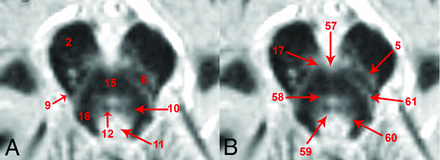

Labeling in the figures emphasizes unambiguous structures that can be identified well on the images. Most of these labeled structures are well-known to clinicians familiar with brain stem anatomy (eg, the medial longitudinal fasciculus). Directly labeled visible structures also can be used to generate more exact indirect localization for other bordering internal brain stem structures. Figure 4 provides a highly detailed example of this approach for the inferior midbrain where the likely positions of multiple additional structures can be estimated relative to the borders and anatomic spaces formed between the medial longitudinal fasciculus, medial lemniscus, and decussation of the superior cerebellar peduncles. Annotation at this level of detail with descriptions of functional relevance is possible throughout the brain stem, but is beyond the scope of this initial report. Other selected examples of indirect localization that may be of general interest include the oculomotor complex (bright region posteromedial to the central tegmental tract in Fig 1A), pedunculopontine nucleus (bright region medial to the medial lemniscus and lateral to the decussation of the superior cerebellar peduncles, in Fig 1B), locus coeruleus (bright region posterior to the central tegmental tract and medial to the superior cerebellar peduncle in Fig 1C), and facial nucleus (bright region posterolateral to the central tegmental tract and medial to the cerebellar peduncles in Fig 1F). An inferior notch along the medial aspect of the left middle cerebellar peduncle with gray matter signal intensity in Fig 2D is the cochlear nucleus.

Direct, unambiguous identification of many myelinated structures in the inferior midbrain (A) also helps improve the spatial accuracy for indirect localization of bordering brain stem nuclei and pathways that are less densely myelinated at this level (B). The ventral trigeminothalamic tract61 is located between the decussation of the superior cerebellar peduncles and medial lemniscus. Subtle dark bumps on the anterior and posterior aspects of the decussation15 are consistent with the rubrospinal17 and tectospinal tracts,58 respectively. The bright midline structure anterolateral to the medial longitudinal fasciculus8 should be the substantia nigra pars compacta.5 The reticular formation60 is the bright region posterolateral to the medial longitudinal fasciculus and central tegmental tract,10 and anterolateral to the periaqueductal gray.11 This region will also contain the locus coeruleus. The trochlear nucleus59 should be along the posterior border of the medial longitudinal fasciculus. The interpeduncular nucleus57 is off-midline anterior to the decussation of the superior cerebellar peduncles. Similar indirect localization can be derived at other brain stem levels, but is beyond the scope of this initial report.